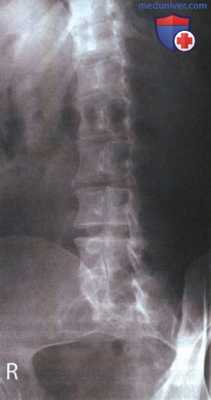

РИСУНОК 1 Рентгенограмма поясничного отдела позвоночника в ПЗ проекции, демонстрирующая правильное его расположение.

• Сколиоз: рис. 4 и 5

РИСУНОК 2 Правильное положение пациента для рентгенографии поясничного отдела позвоночника в ПЗ проекции. РИСУНОК 3 Рентгенограмма поясничного отдела позвоночника в ПЗ проекции. Левая сторона располагалась к ПИ ближе, чем правая.

РИСУНОК 4 Рентгенограмма поясничного отдела позвоноч ника в ПЗ проекции при выраженном сколиозе. РИСУНОК 5 Рентгенограмма поясничного отдела позвоночника в ПЗ проекции при слабом сколиозе. РИСУНОК 6 Рентгенограммы поясничного отдела позвоночника пациента в боковой и ПЗ проекциях. Показано положение межпозвонковых щелей. РИСУНОК 7 Положение ЦЛ и поясничных позвонков при разогнутых нижних конечностях. РИСУНОК 8 Рентгенограмма поясничного отдела позвоночника в ПЗ проекции при разогнутых тазобедренных и коленных суставах. РИСУНОК 9 Положение ЦЛ и поясничных позвонков при согнутых нижних конечностях.

в) Сколиоз. Тела поясничных позвонков также могут казаться ротированными при сколиозе. Выраженный сколиоз (рис. 4) отличить от ротации достаточно легко в отличие от небольшого сколиоза (рис. 5). Несмотря на то, что как при сколиозе, так и при ротации расстояние между корнями дут позвонков и остистыми отростками будет разным, существуют определенные признаки, по которым оба состояния можно различить.

Так, при ротации продольная ось позвоночного столба остается прямой, а при сколиозе позвоночный столб отклоняется вбок. Если на рентгенограмме поясничные позвонки ротированы, это могло произойти вследствие ротации верха или низа туловища.

Средние поясничные позвонки (L3 и L4) могут быть ротированы только при ротации нижних грудных, верхних или нижних поясничных позвонков. Напротив, при сколиозе на рентгенограмме могут быть ротированы только средние поясничные позвонки.